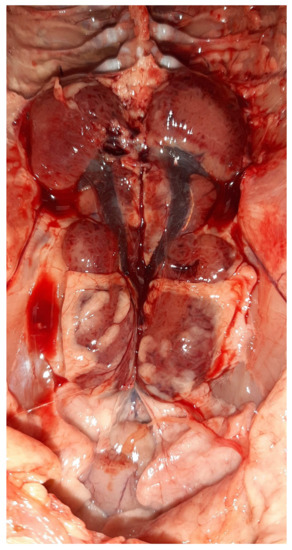

Figure 5.

Post-mortem examination of a 23-day-old broiler chicken from the Flock A. The liver dominates in the visceral capacity with the lobes of the organ appearing swollen with a marble-like pattern ranging from pale and yellowish to red-dark.

On necropsy, most of the chickens had yellowish mucoid diarrhea soiling the feather of the cloaca (Figure 3). Icteric skin and subcutaneous fat were notable in affected birds, while petechial hemorrhages on leg and breast muscles were rarely recorded (Figure 3). During evisceration, the liver dominated the visceral capacity with the lobes of the organ appearing swollen with a marble-like pattern ranging from pale and yellowish to red-dark (Figure 4 and Figure 5). Similarly, kidneys were pale, oedematous, and mottled, enlarged with urates accumulation in the ureters (Figure 6). In many birds, the pancreas was also affected and was slightly inflamed with necrotic foci spotting the surface of the organ (Figure 7). Finally, some birds presented a moderately atrophic Bursa of Fabricius and thymus.